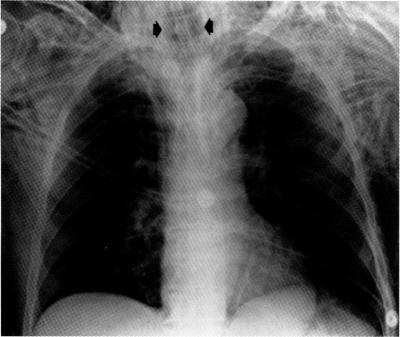

甲状腺淋巴瘤治疗期间的致命性气管溶解

Lethal tracheal dissolution during treatment for thyroid lymphoma.

• A case of primary thyroid T cell lymphoma leading to lethal tracheal perforation during chemotherapy is described.

本文描述了一例原发性甲状腺T细胞淋巴瘤患者在化疗期间发生致命性气管穿孔的病例。